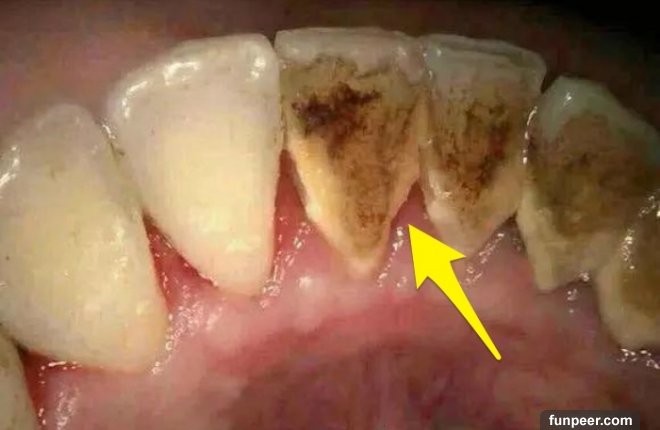

什麼是牙結石牙結石又稱牙石,通常存在於唾液腺開口處的牙齒表面。如下顎前牙的舌側表面,上顎後牙的頰側表面和牙齒的頸部,以及口腔黏膜運動不到的牙齒表面等處。牙結石最開始是乳白色的軟垢,通過逐漸鈣化變硬。它是由75%的磷酸鈣,15%~25%的水、有機物、磷酸錳、礦酸鈣及微量的鉀、鈉、鐵所構成。牙結石通常呈現出黃色、棕色、或黑色等,有的與自然牙顏色相近,有的則明顯可見差異。

與口水濃度有關,濃度愈大,愈易沉澱。另外,牙結石形成的速度、形態和硬度因人而異,一般來說新生牙結石只需12-15小時。快速形成的牙結石要比慢慢形成的牙結石要軟且碎。牙結石的危害牙結石一旦鈣化,就等同於在口腔中落地生根,建立了生存的基地。但這位大惡魔並不會就此止步,而是繼續開枝散葉、呼朋引伴,隨著時間的推移越積越多、越級越厚,並逐漸向牙頸部位發展,形成更為隱形也更為可怕的“齦下結石”。

牙結石從牙冠逐漸向下蔓延,牙結石每進步一些,牙槽骨就萎縮一些,久而久之,牙齒就逐漸松動,牙結石便見縫插針,逐漸蔓延到牙根部位。對口腔而言,結石是一種異物,它的存在本身就會不斷刺激牙周組織並壓迫牙齦,影響口腔局部血液循環,造成牙周組織病菌感染,引起牙齦發炎萎縮,形成牙周袋。當牙周袋形成後,食物殘渣、牙菌斑和結石等更易堆積,進一步的破壞更深的牙周膜,如此不斷的惡性循環的結果,終至牙周支持組織全部破壞殆盡,牙齦出血、牙周疾病等隨之而來。總而言之,如不能及時清除,被牙結石纏上的牙齒最終逃脫不了潰爛脫落的命運。作為口腔健康的一級殺手,牙結石的存在不容忽視。值得注意的是,在牙結石形成之初由於硬度較小,使用口腔清潔或刷牙等方法往往較容易清除,而隨著日積月累的鈣化、牙結石在口腔中緊密附著,普通的刷牙或口腔清潔方法便難以將其去除了。相信有的朋友在閱讀文章的時候就已經按耐不住“攬鏡自照”來確認自己口中有沒有被牙結石入侵了吧?不用過分擔心,接下來將傳授給大家對抗之法,幫助大家戰勝這位牙周疾病的罪魁禍首、口腔中的大惡魔。牙結石的清除方法經過鈣化的牙結石難以通過刷牙等傳統方式清潔,但口腔潔治可以做到,也就是通常說的洗牙。洗牙有手工掛治和超聲潔治兩種,目前大部分醫院和診所采用的是超聲潔牙。手工刮治通過比較精細的齦下刮治器刮除牙齒附著的牙石和菌斑。而超聲潔牙機則通過高頻率震蕩傳導至特制工作尖,將能量集中在工作尖並釋放,對頑固堅硬的牙結石產生較大的衝擊力,並將其震碎,使其從附著的牙面脫落。同時,超聲震蕩產生的水霧將環繞在工作尖的周圍,將牙結石的碎屑衝洗殆盡。